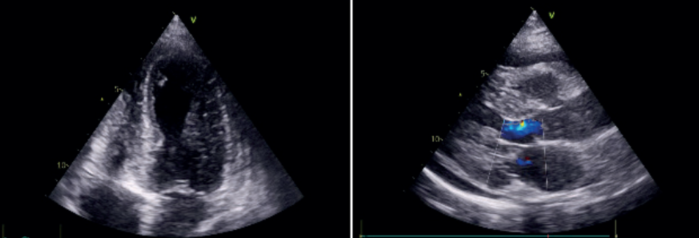

La radiografía de tórax mostró escaso edema intersticio-alveolar difuso. Se realizó ecocardiograma transtorácico (ETT) en el que se observó un remodelado concéntrico del ventrículo izquierdo (VI), hipoquinesia de los segmentos apicales a predominio septal y anterior con una fracción de eyección del VI (FEVI) levemente disminuida (50%) y derrame pericárdico leve (figura 2).

Se realizó un nuevo ETT que mostró aquinesia de todos los segmentos apicales y de los segmentos medios de la pared anterior y septal anterior, FEVI 38%, insuficiencia mitral e insuficiencia tricuspídea moderadas, hipertensión pulmonar (presión sistólica de la arteria pulmonar estimada en 62 mmHg) y derrame pericárdico leve sin repercusión hemodinámica.